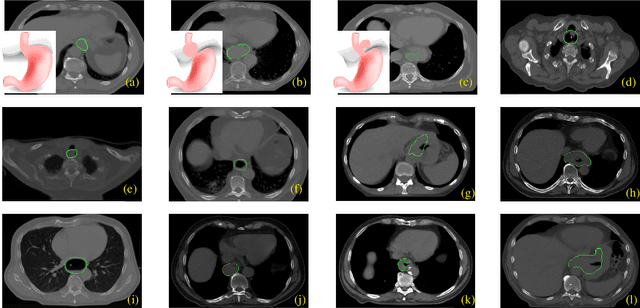

Abstract:Manual or automatic delineation of the esophageal tumor in CT images is known to be very challenging. This is due to the low contrast between the tumor and adjacent tissues, the anatomical variation of the esophagus, as well as the occasional presence of foreign bodies (e.g. feeding tubes). Physicians therefore usually exploit additional knowledge such as endoscopic findings, clinical history, additional imaging modalities like PET scans. Achieving his additional information is time-consuming, while the results are error-prone and might lead to non-deterministic results. In this paper we aim to investigate if and to what extent a simplified clinical workflow based on CT alone, allows one to automatically segment the esophageal tumor with sufficient quality. For this purpose, we present a fully automatic end-to-end esophageal tumor segmentation method based on convolutional neural networks (CNNs). The proposed network, called Dilated Dense Attention Unet (DDAUnet), leverages spatial and channel attention gates in each dense block to selectively concentrate on determinant feature maps and regions. Dilated convolutional layers are used to manage GPU memory and increase the network receptive field. We collected a dataset of 792 scans from 288 distinct patients including varying anatomies with \mbox{air pockets}, feeding tubes and proximal tumors. Repeatability and reproducibility studies were conducted for three distinct splits of training and validation sets. The proposed network achieved a $\mathrm{DSC}$ value of $0.79 \pm 0.20$, a mean surface distance of $5.4 \pm 20.2mm$ and $95\%$ Hausdorff distance of $14.7 \pm 25.0mm$ for 287 test scans, demonstrating promising results with a simplified clinical workflow based on CT alone. Our code is publicly available via \url{https://github.com/yousefis/DenseUnet_Esophagus_Segmentation}.